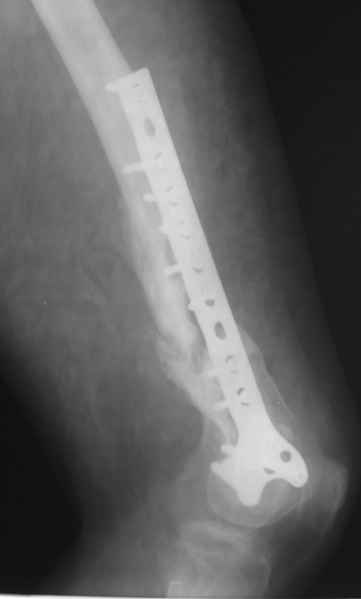

Обратился на консультацию больной. 24 декабря 2009г. попал в ДТП, получил переломы правого бедра, правой ключицы и левой голени. 28 января 2010г. выполнен металлоостеосинтез правой бедренной кости пластиной. 8 апреля 2010г. выявлен неполный перелом пластины, на половину, по одному из отверстий для винтов. 15 апреля 2010г., на фоне сепсиса, выполнен реостеосинтез со свободной костной аутопластикой зоны перелома. Ранний послеоперационный период осложнился нагноением гематомы в месте операции. Последняя была эвакуирована с сохранением фиксатора. Рана зажила. Через два месяца открылся свищ с незначительным слизисто-гнойным отделяемым, функционирует до сих пор без изменений. При осмотре – в центре послеоперационного рубца свищ, около 2 мм в диаметре, со скудным отделяемым. Зонд, введенный в свищевой ход, доходит до металлоконструкции. Коленный сустав отечный, активные и пассивные движения в нем резко ограничены и составляют: сгибание – 100 градусов, разгибание – 160. Выполнили рентгенографию – ложный сустав, остеомиелит, пластина установлена слишком низко, «внутрисуставно», что вызывает постоянный синовиит и отек параартикулярных тканей. Хотелось бы обсудить тактику дальнейшего лечения: 1. Считаем, что у молодого человека, милиционера по профессии, спасти коленный сустав другими способами, кроме БИОС, маловероятно. 2. Чему отдать предпочтение – обычный вариант или ретроградный? С уважением, Юрий Алексеевич Булахтин